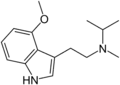

| 4-MeO-MiPT | artificial | 4-OCH3 | CH3 | CH(CH3)2 | 4-methoxy-N-methyl-N-isopropyltryptamine | 96096-53-6 |